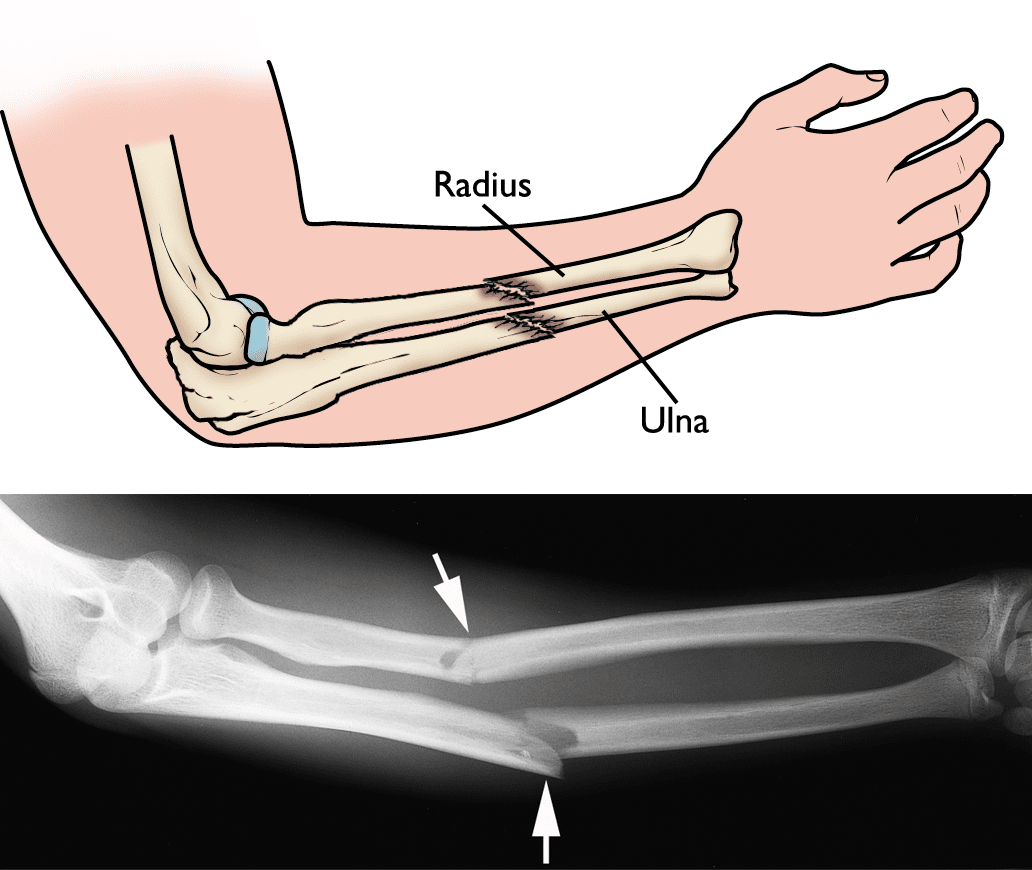

By rotating around the longitudinal axis, the radius is essential for the pronation and supination . Forearm Fracture Orthopaedic Trauma Association Ota

Forearm Fracture Orthopaedic Trauma Association Ota from ota.org